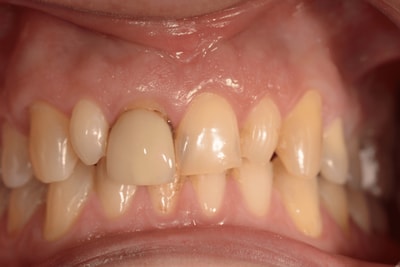

Situation Initiale